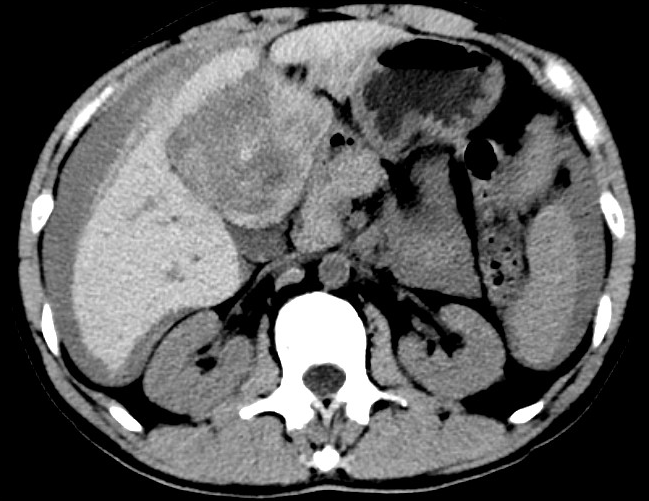

放下電話的白葦急赴消內(nèi)三搶救室會(huì)診,經(jīng)仔細(xì)查體、對(duì)患者腹部CT進(jìn)行詳細(xì)閱片、綜合評(píng)估患者后,考慮患者是肝占位破裂出血?;颊卟∏槭志o急、一刻也不容耽誤,需立刻急診行肝動(dòng)脈造影 栓塞術(shù)進(jìn)行止血治療,在與患者家屬溝通后,立即通知消化介入室準(zhǔn)備急診手術(shù)。

入手術(shù)室時(shí),患者神志迷糊,口唇干燥、重度貧血貌,心電監(jiān)護(hù)提示:心率140-160次/分,血壓70/43mmHg,這是失血性休克的表現(xiàn)!白葦快速建立靜脈通道緊急給予輸血,升壓,止血等液,立即給予肝動(dòng)脈造影,術(shù)中發(fā)現(xiàn)肝左葉疑似腫瘤病灶、病灶周圍血管分支有造影劑外溢,考慮血管破裂出血,迅速給予栓塞微球進(jìn)行肝動(dòng)脈栓塞。整個(gè)手術(shù)過(guò)程不足20分鐘,術(shù)后即刻患者心率降至100-110次/分、血壓升至90/60mmHg。

術(shù)后給予積極抗炎,止血,保肝、利尿等對(duì)癥治療,復(fù)查血常規(guī)提示活動(dòng)性出血停止后,在超聲引導(dǎo)下行腹腔穿刺引流術(shù),術(shù)后3天共引流出血性腹水約4000ml?;颊呓?jīng)復(fù)查各項(xiàng)指標(biāo)均趨于正常,復(fù)查CT提示腹腔積血已基本吸收,患者康復(fù)出院。